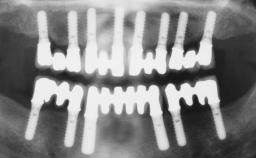

Immediate Loading of Six Implants in the Maxilla and Final Restoration with a Full-Arch Gold/Ceramic FDP Involving the Concept of Tilted Implants

A 61-year-old male patient with a failing fixed maxillary rehabilitation and a fixed mandibular rehabilitation requested a new fixed maxillary rehabilitation. The patient was wearing a temporary metal-reinforced maxillary bridge inserted two years before the consultation. He reported that his previous dentist did not want to insert a definitive framework because he considered the residual teeth to have a negative prognosis. The patient reported a history of recurrent caries and endodontic complications as the main reason for the previous extractions. The anamnesis was negative for periodontal disease and bruxism. The patient’s chief compliant was the mobility of his maxillary prosthesis, which needed to be re-cemented frequently, and discomfort during chewing.Moreover, the patient was not satisfied with the esthetic appearance of his maxillary teeth, which he found too long. The patient asked for a stable and comfortable fixed maxillary rehabilitation and firmly rejected any removable solution.

# of Implants 6

Type of Implants One-Piece|Reduced-Diameter

Defining Characteristics Fully edentulous upper jaw to be rehabilitated with four or more implants

Modality Fixed hybrid bridge on 5+ implants

Bone Volume Deficient horizontally, allowing simultaneous augumentation

Loading Protocol Immediate